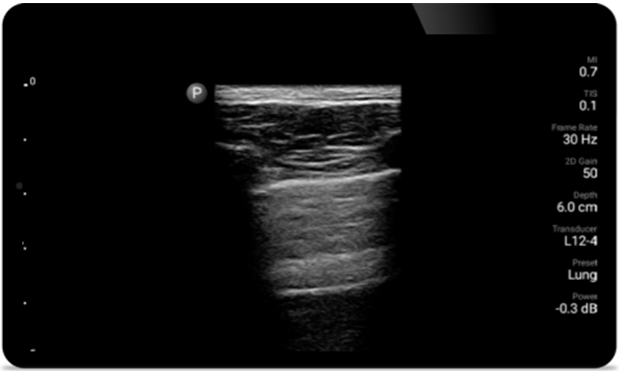

Breathe easier with Lumify

Lumify can help assess patients faster and improve accuracy when diagnosing common causes of dyspnea and other lung conditions.

• 4 to 1 MHz extended operating frequency range • 2D, color Doppler, M-mode, advanced XRES and multivariate harmonic imaging • High-resolution imaging for abdominal and cardiac applications: Cardiac, OB/GYN, Lung, Abdomen and FAST imaging preset optimizations Lumify aids life-saving technology in prehospital setting